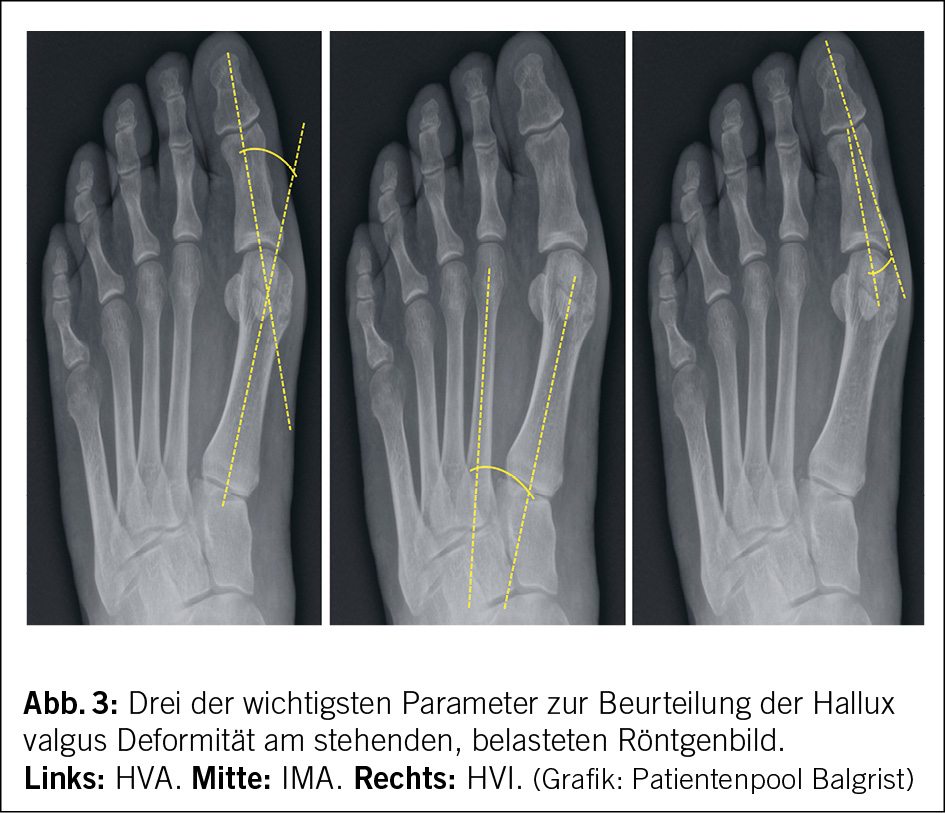

Als primär diagnostisches Tool wird das konventionelle belastete Röntgenbild durchgeführt (6, 16, 17). Es können einige radiologische Winkel bestimmt werden, so zum Beispiel zwischen dem Schaft des Metarsale I und dem Schaft der proximalen Phalanx, dies ist der klassische Hallux valgus Winkel (HVA), der Winkel zwischen den ersten beiden Metatarsale (IMA) und der Winkel zwischen den Phalangen (HVI) (Abb. 3). Schnittbildgebungen wie MRI oder CT werden im Normalfall nicht benötigt. Ein MRI wird jedoch durchgeführt, wenn zum Beispiel der Knorpelzustand am MTP I beurteilt werden muss, da schon eine Arthrose bestehen könnte oder wenn Schmerzen in den Zwischenzehenräumen bestehen und ein Mortonneurom vermutet wird (18). Zunehmend können auch stehende CT Bildgebungen durchgeführt werden, dies zum einen um die Rotation des Metatarsale und die Position der Sesambeine genauer beurteilen zu können, zum anderen gibt es eine sehr potente Übersicht des Fusses unter Belastung, was die präoperative Vorbereitung stark präzisieren kann (19).